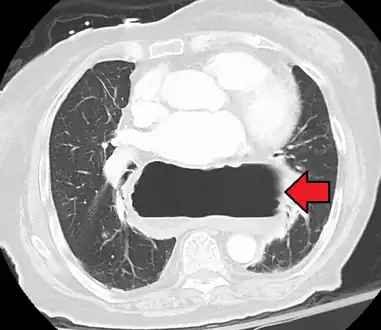

A hiatal hernia as seen on CT

A large hiatal hernia as seen on CT imaging